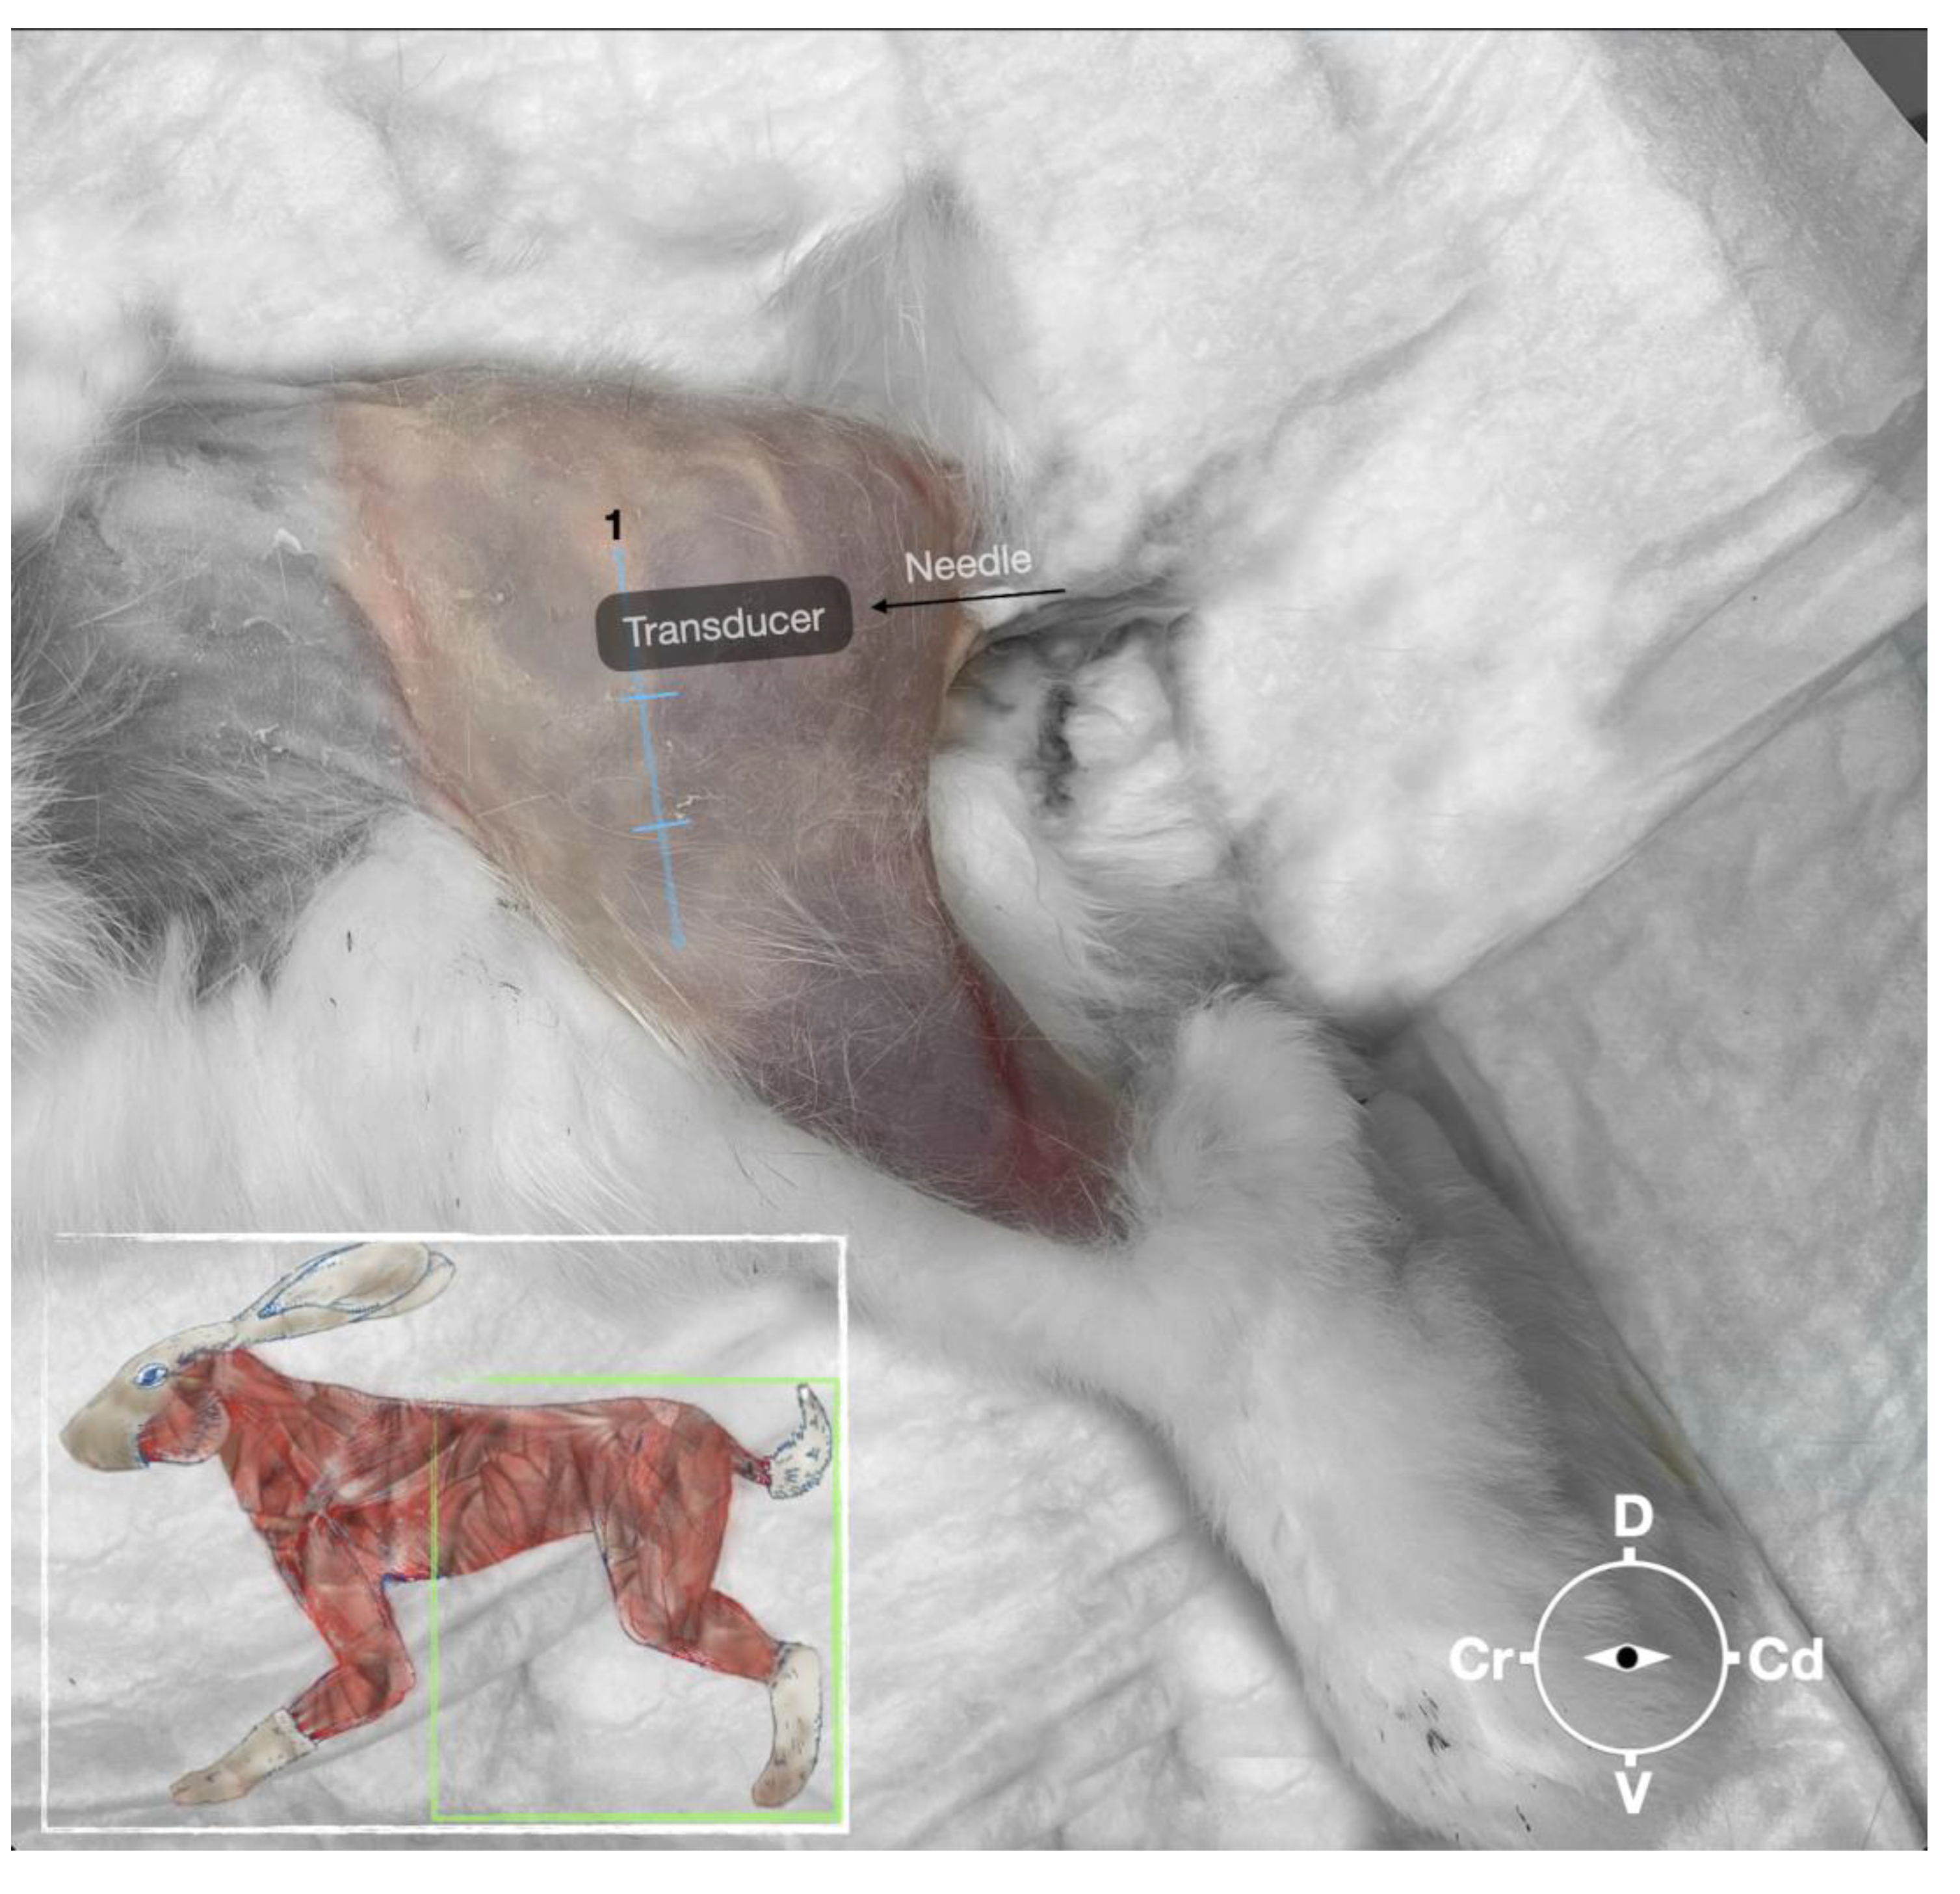

Figure 2. Position of the cadaver, anatomical landmarks for initial ultrasound transducer placement and the needle insertion for the perineural sciatic nerve injection. The blue line indicates the long-axis of the femur. 1, Major trochanter of the femur, Cr, cranial; Cd, caudal; D, dorsal, V, ventral.

First, the cadaver was positioned in lateral recumbency. Then, the area of interest was clipped, and the hair was removed. A 18-4 MHz linear transducer (L 18-4,Konica Minolta, USA) attached to an ultrasound machine (HS1, Konica Minolta, USA) was used and ultrasound gel (Softa-Man, ViscoRub, B. Braun, Austria) was applied to facilitate acoustic coupling. The transducer was placed in transverse position, at the level of the proximal third of the femur but caudal to the bone with a window of interest set at a depth of 3 cm to optimize the image. Then, the transducer was slightly rotated clock or anticlockwise to obtain a transverse image of the sciatic nerve (Figure 1). A 50 mm 22 gauge insulated needle (Sonoplex Stim Cannula, Pajunk Medical Produkte GmbH, Germany) prefilled with a 1:1 solution of new methylene blue (MethyleneBlue1%w/vaq.soln, AlfaAesar, Thermo FischerGmbH, Germany) and lidocaine (Xylanest purum 2%, Gebro Pharm GmbH, Austria) (L-NMB) was inserted using an in-plane approach. The needle was inserted at the caudal end of the transducer and advanced in-plane under sonographic guidance through the biceps femoris muscle in a cranio-medial direction towards the sciatic nerve (Figure 2). The needle was advanced until its tip punctured the muscular fascia enveloping the sciatic nerve (Figure 3). A test volume of 0.05 ml of L-NMB was injected to confirm adequate distribution inside the interfascial space that contained the sciatic nerve. The remaining volume of 0.15ml/kg was then injected perineurally around the sciatic nerve.